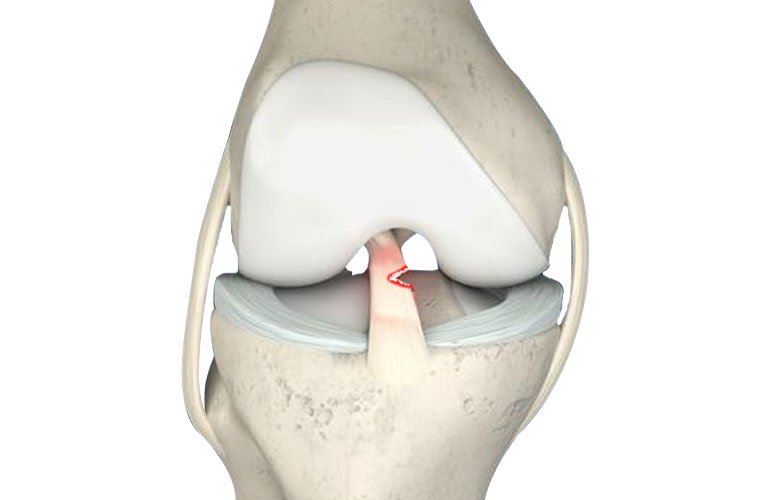

- Partial Tear Confirmation : The first step is confirming the diagnosis of a partial ACL tear through clinical evaluation, physical examination, and diagnostic imaging like MRI.

- Extent of Injury : The size and location of the partial tear are crucial in determining whether non-surgical options are viable. Small, isolated tears are more amenable to non-surgical treatment.

A First-Line Treatment Image-guided Comprehensive PRP with Prolotherapy is gaining recognition as a standard first-line treatment for partial ACL tears. This innovative approach combines two regenerative therapies to stimulate the body’s natural healing processes and address the root cause of the injury.